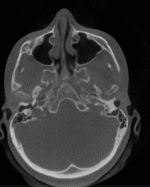

El CBCT (Cone Beam Computed Tomography) o tomografía volumétrica de haz cónico es una tecnología de imagen 3D que permite visualizar estructuras craneofaciales con altísima precisión.

A diferencia de una radiografía tradicional (2D), el CBCT:

- Captura volumen completo (3D)

- Permite ver hueso, dientes y vías aéreas

- Usa menor radiación que un TAC médico convencional

- Es ideal para diagnóstico funcional, estructural y anatómico

BENEFICIOS EN VÍAS AÉREAS

Aquí es donde el CBCT se vuelve oro puro para tu práctica:

- Evaluación volumétrica real

- Volumen total de vía aérea (mm³)

- Área mínima (zona crítica de colapso)

- Segmentación:

- Nasal

- Nasofaríngea

- Orofaringe

- Análisis nasal detallado

- Cornetes (hipertrofia)

- Desviación septal

- Válvula nasal (clave en tu enfoque)

Puedes objetivar obstrucción nasal funcional

- Adenoides (muy importante en niños)

- Tamaño real

- Relación con vía aérea

- Grado de obstrucción

Mucho más preciso que radiografía lateral